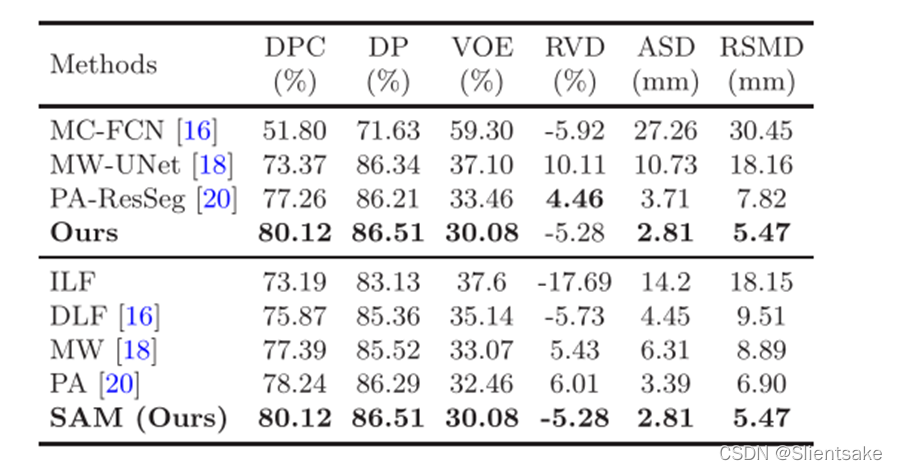

比较先进的:

为了验证该方法的有效性,将其与目前最先进的三种多相lits方法进行了比较:(1)MC-FCN方法简单地将多相特征连接到FCN分类层之前;(2) MW-UNet,训练U-Net各层各阶段的具体权值;(3) PA-ResSeg,引入信道注意机制,在ResNet的特定层对各信道的多相特征重新加权。

表1:方法和最新技术之间的定量比较

图3为对比实验的可视化示例。可以观察到MC-FCN产生的结果很差,因为它粗暴地连接了来自不同阶段的决策级特征。这些原始的多相特性可能会带来冲突或干扰因素,从而导致性能较差。MW-UNet和PA-ResSeg的结果更好,能够捕获肿瘤的粗糙形状。然而,像素的分割,特别是在肿瘤边界,是不令人满意的。这是因为两种方法都忽略了特征的空间融合,导致对多相位特征的融合不够充分。此外,它们没有提供任何处理不确定性问题的策略,这使得边界像素分类变得困难。相比而言,作者的方法鼓励逐像素的相间相互作用,并引入了不确定的区域内填补机制,证明了该方法在DPC、DP、VOE、ASD和RSMD评分中获得了最佳值(见表1)。

此外,为了验证提出的交叉相位融合策略(SAM模块),将其与其他四种融合方法进行了比较:(1)输入级融合(ILF)策略,该策略将多相位图像连接在输入端;(2)MC-FCN中使用的决策级融合(DLF)策略;(3) MW UNet中采用的模态加权(MW)策略和PAResSeg中采用的相位注意(PA)策略。为了保证比较的公平性,除了替换特征聚合模块外,所有融合模块都插入到所提出的网络中。如表1所示。SAM策略更好地利用了多相位信息,并且优于其他融合策略。